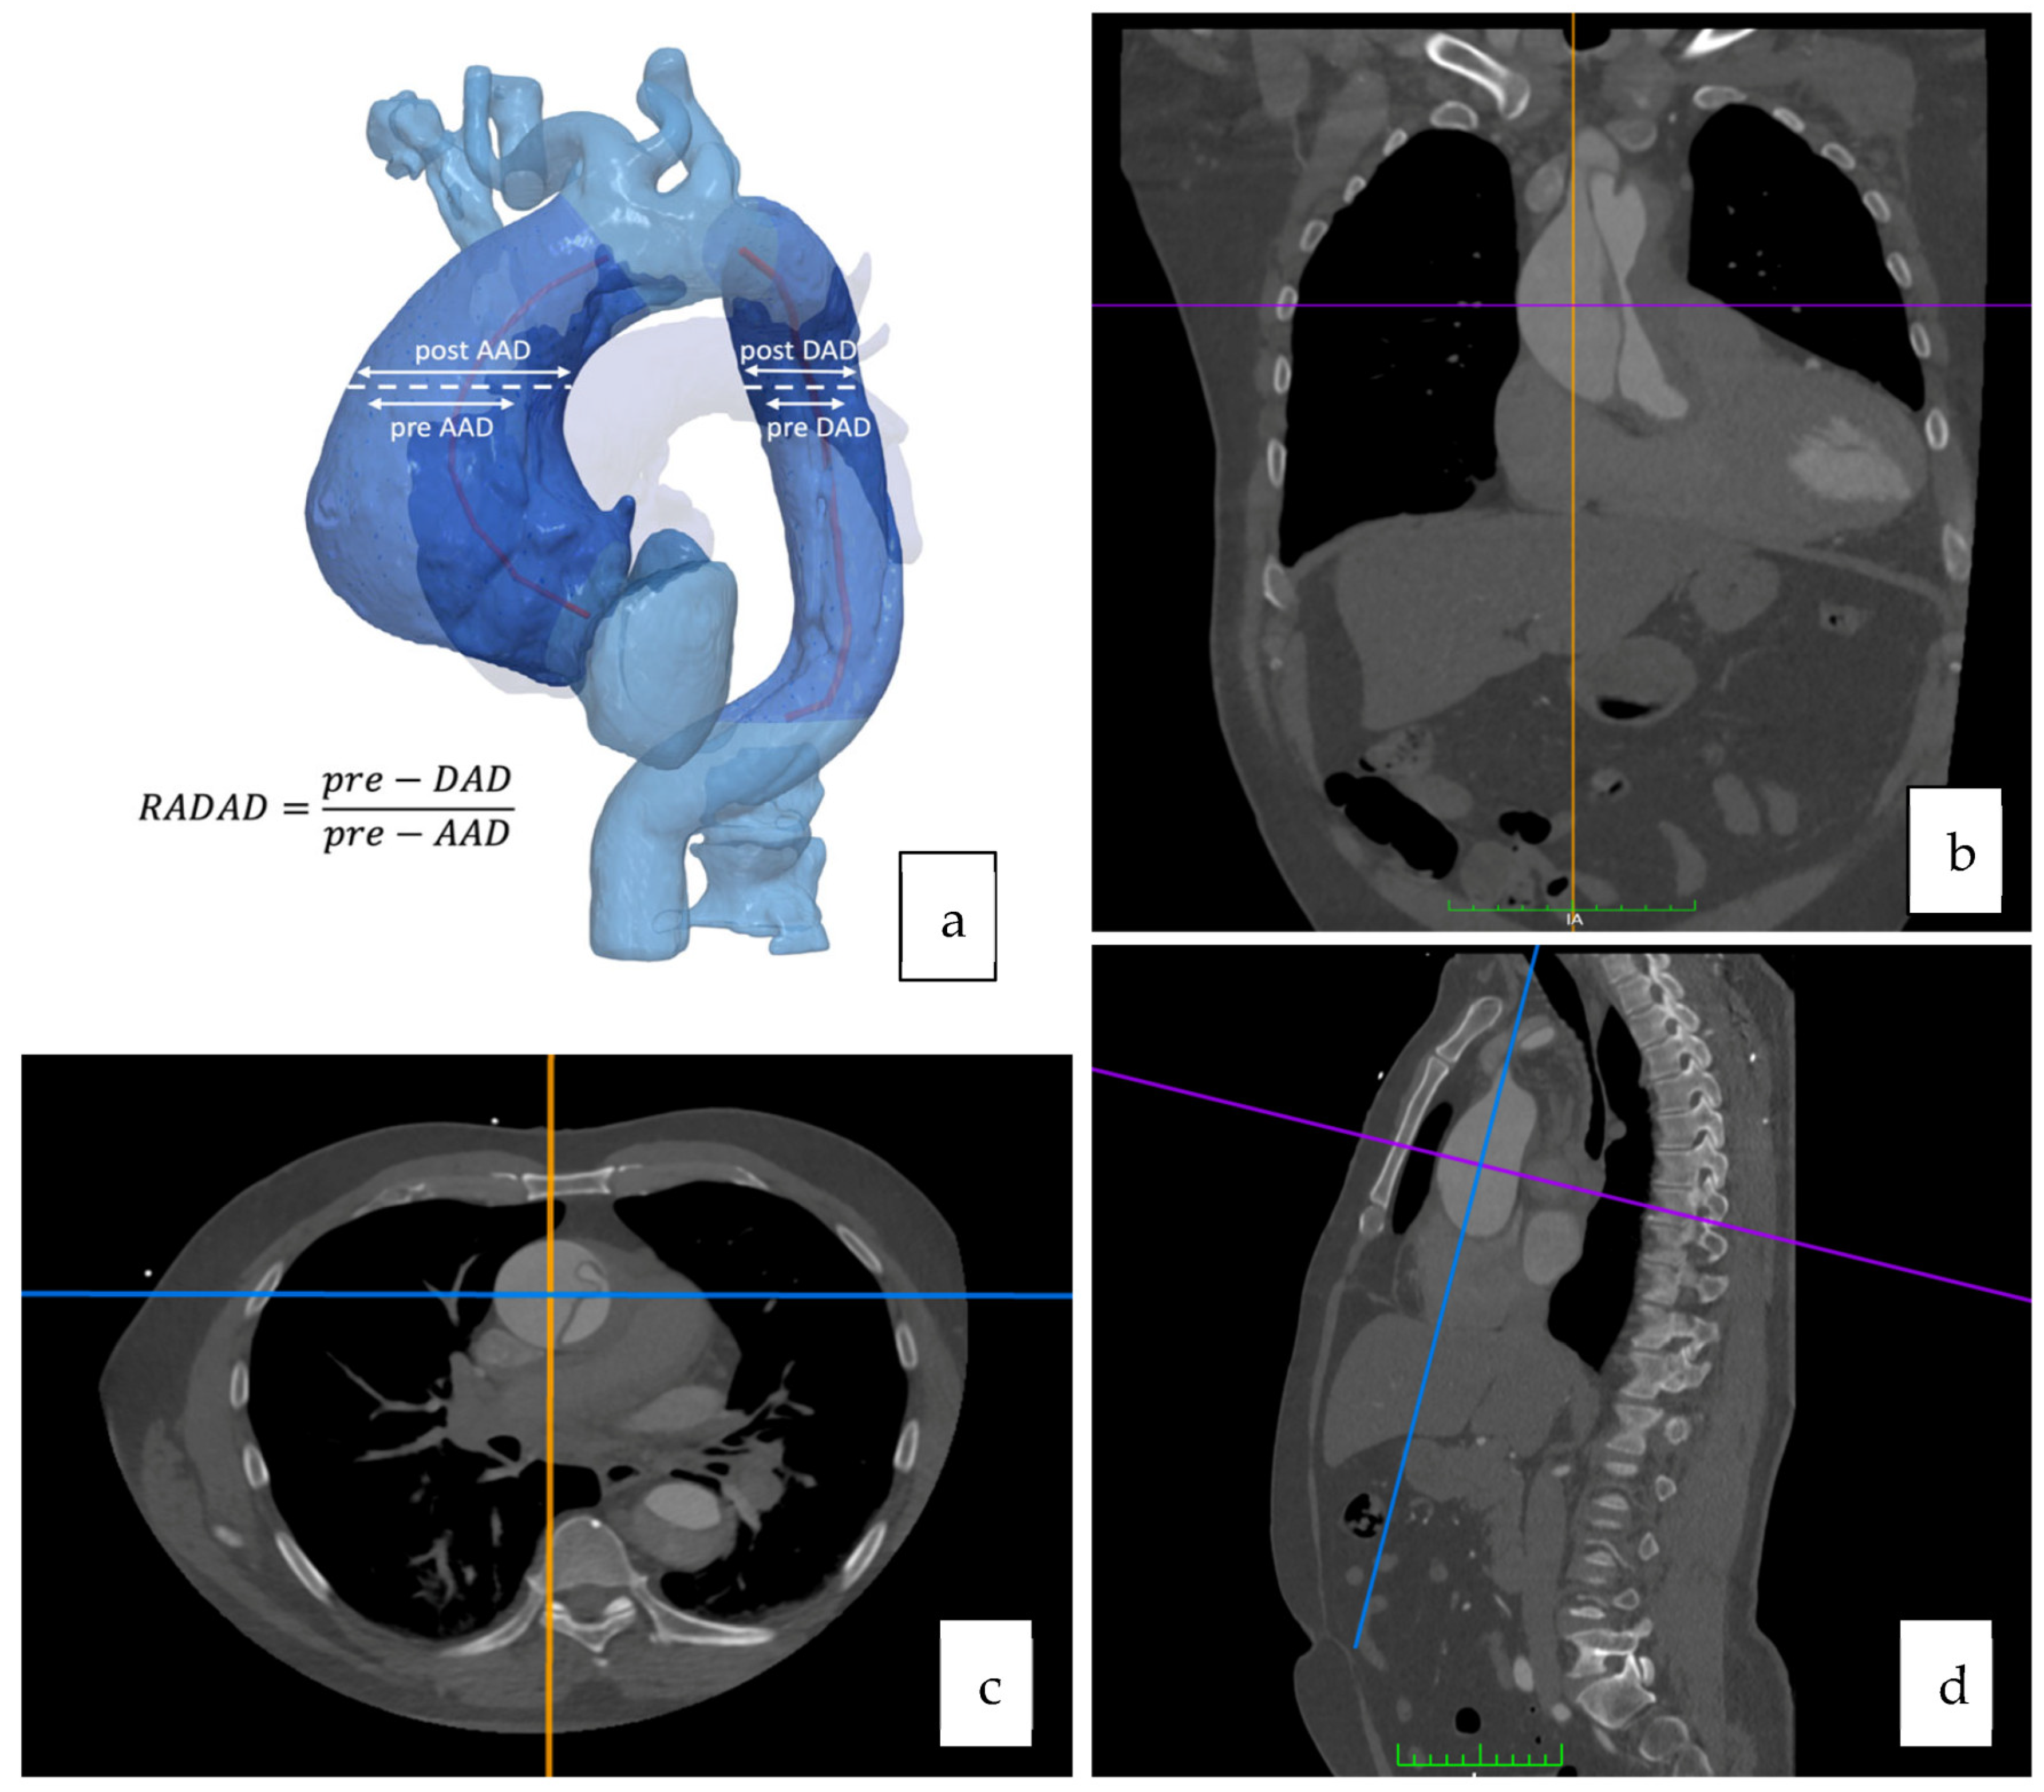

2.3. Imagining Analysis